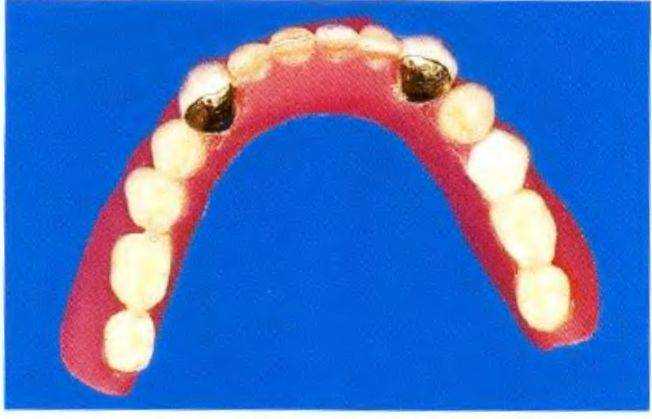

помощью шаблонов (рис. 1-9v) и припасовали изогнутую балку к пазам в головках имплантатов (рис. 1-9w). Поскольку временные имплантаты довольно сложно установить на одном уровне, потребовалось сошлифовать изогнутую балку для ее адекватной припасовки (рис. 1-9х и 1-9у).

Поверх имплантатов установили белые пластмассовые направляющие колпачки и зафиксировали балку адгезивом световой полимеризации (рис. с 19z по 1-9сс). Затем провели сошлифовывание и адаптацию протеза нижней челюсти (рис. с 1-9dd по 1-9ff).

Рис. 1-9z. Окклюзионный вид установленной балки

Рис. 1-9аа. Окклюзионный вид после установки направляющих колпачков

После этого протез перебазировали с помощью самоотверждаемой пластмассы и отполимеризовали балку внутри протеза, закрыв поднутрения красными резиновыми кольцами (см. рис. 1-9bb). На рис. с 1-9gg по 1-9ii продемонстрированы различные поверхности подготовленного протеза, который надежно фиксировался в полости рта пациента (рис. 1 -9jj).